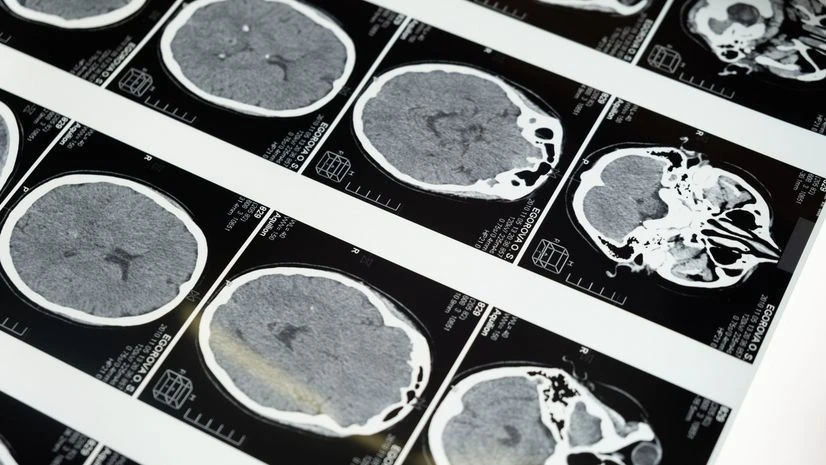

Researchers also found that the characteristics of a particular type of dementia changed following Covid-19, and both degenerative and vascular dementia started behaving like mixed dementia both clinically and radiologically.

The rapid progression of dementia, the addition of further impairments/deterioration of cognitive abilities, and the increase or new appearance of white matter lesions suggest that previously compromised brains have little defence to withstand a new onslaught (that is, a "second hit" like infection/dysregulated immune response and inflammation), they explained.